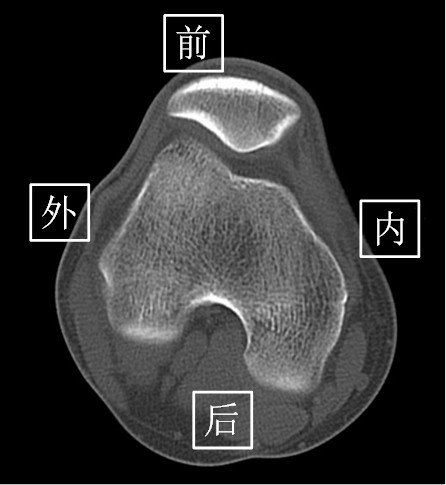

CT扫描可以通过计算机软件对图像进行处理,实现多平面重建。这意味着医生可以从不同的角度观察病变,从而更全面地了解病情。与X光相比,CT的多平面重建技术为诊断提供了更多可能性。

2. 多平面重建:CT数据可以通过计算机处理,生成冠状面、矢状面和任意角度的图像,为医生提供多角度观察病变的机会。

3. 三维成像:CT可以生成三维图像,有助于更直观地理解病变的位置、大小和形态。